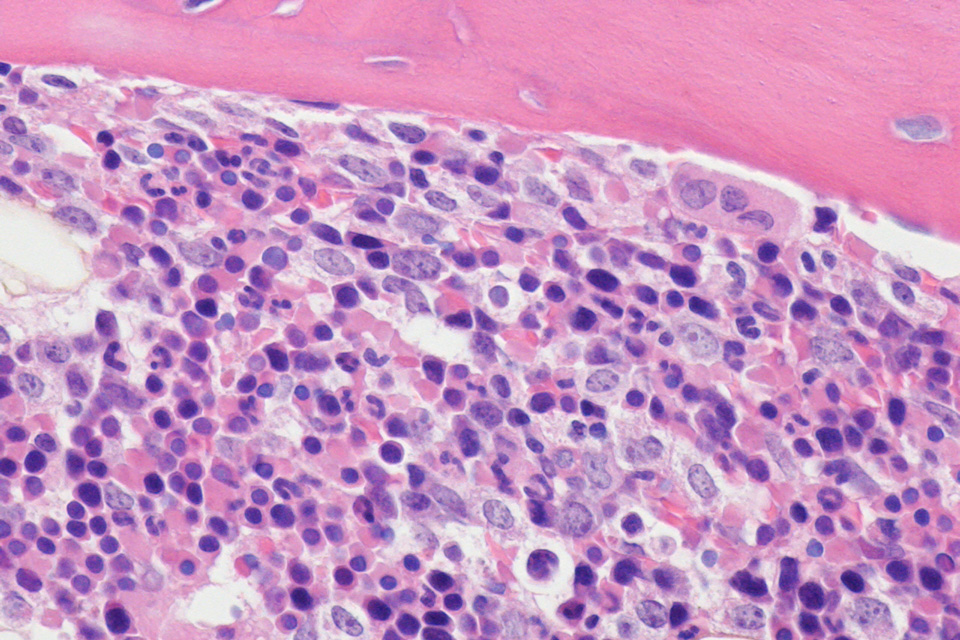

Histology

Purdue’s full-service histology laboratory, supported by the College of Veterinary Medicine, provides general histology, immunohistochemistry, frozen sectioning, decalcified and undecalcified bone histology, and slide digitization services. It also manages a large and small animal necropsy room. The laboratory may collaborate with investigators in the development of new techniques and in the characterization of animal models (e.g. phenotyping of genetically altered mice). Expertise in the processing of bone and implants is available.